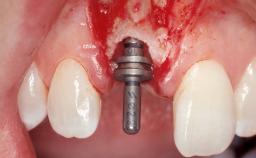

Immediate Placement of an Implant in a Maxillary Left Central Incisor Site

A 33-year-old female patient presented with an upper left central incisor that required extraction after a failed endodontic therapy. The tooth had been traumatized when the patient was a teenager and had undergone several endodontic treatments, including two apicectomy procedures. The patient was in good health and did not smoke. Clinical examination showed that the patient had a high lip line. In full smile, the gingival margins of the upper teeth were visible to the first molars. The gingival margins of central incisors 11 and 21 were only just showing. Examination of tooth 21 confirmed that the tooth was mobile and had hypererupted by 1 mm.

Type of Implants One-Piece

Attachment One-Piece

Placement Protocol Immediate implant placement

Tooth Site Maxillary incisor or canine